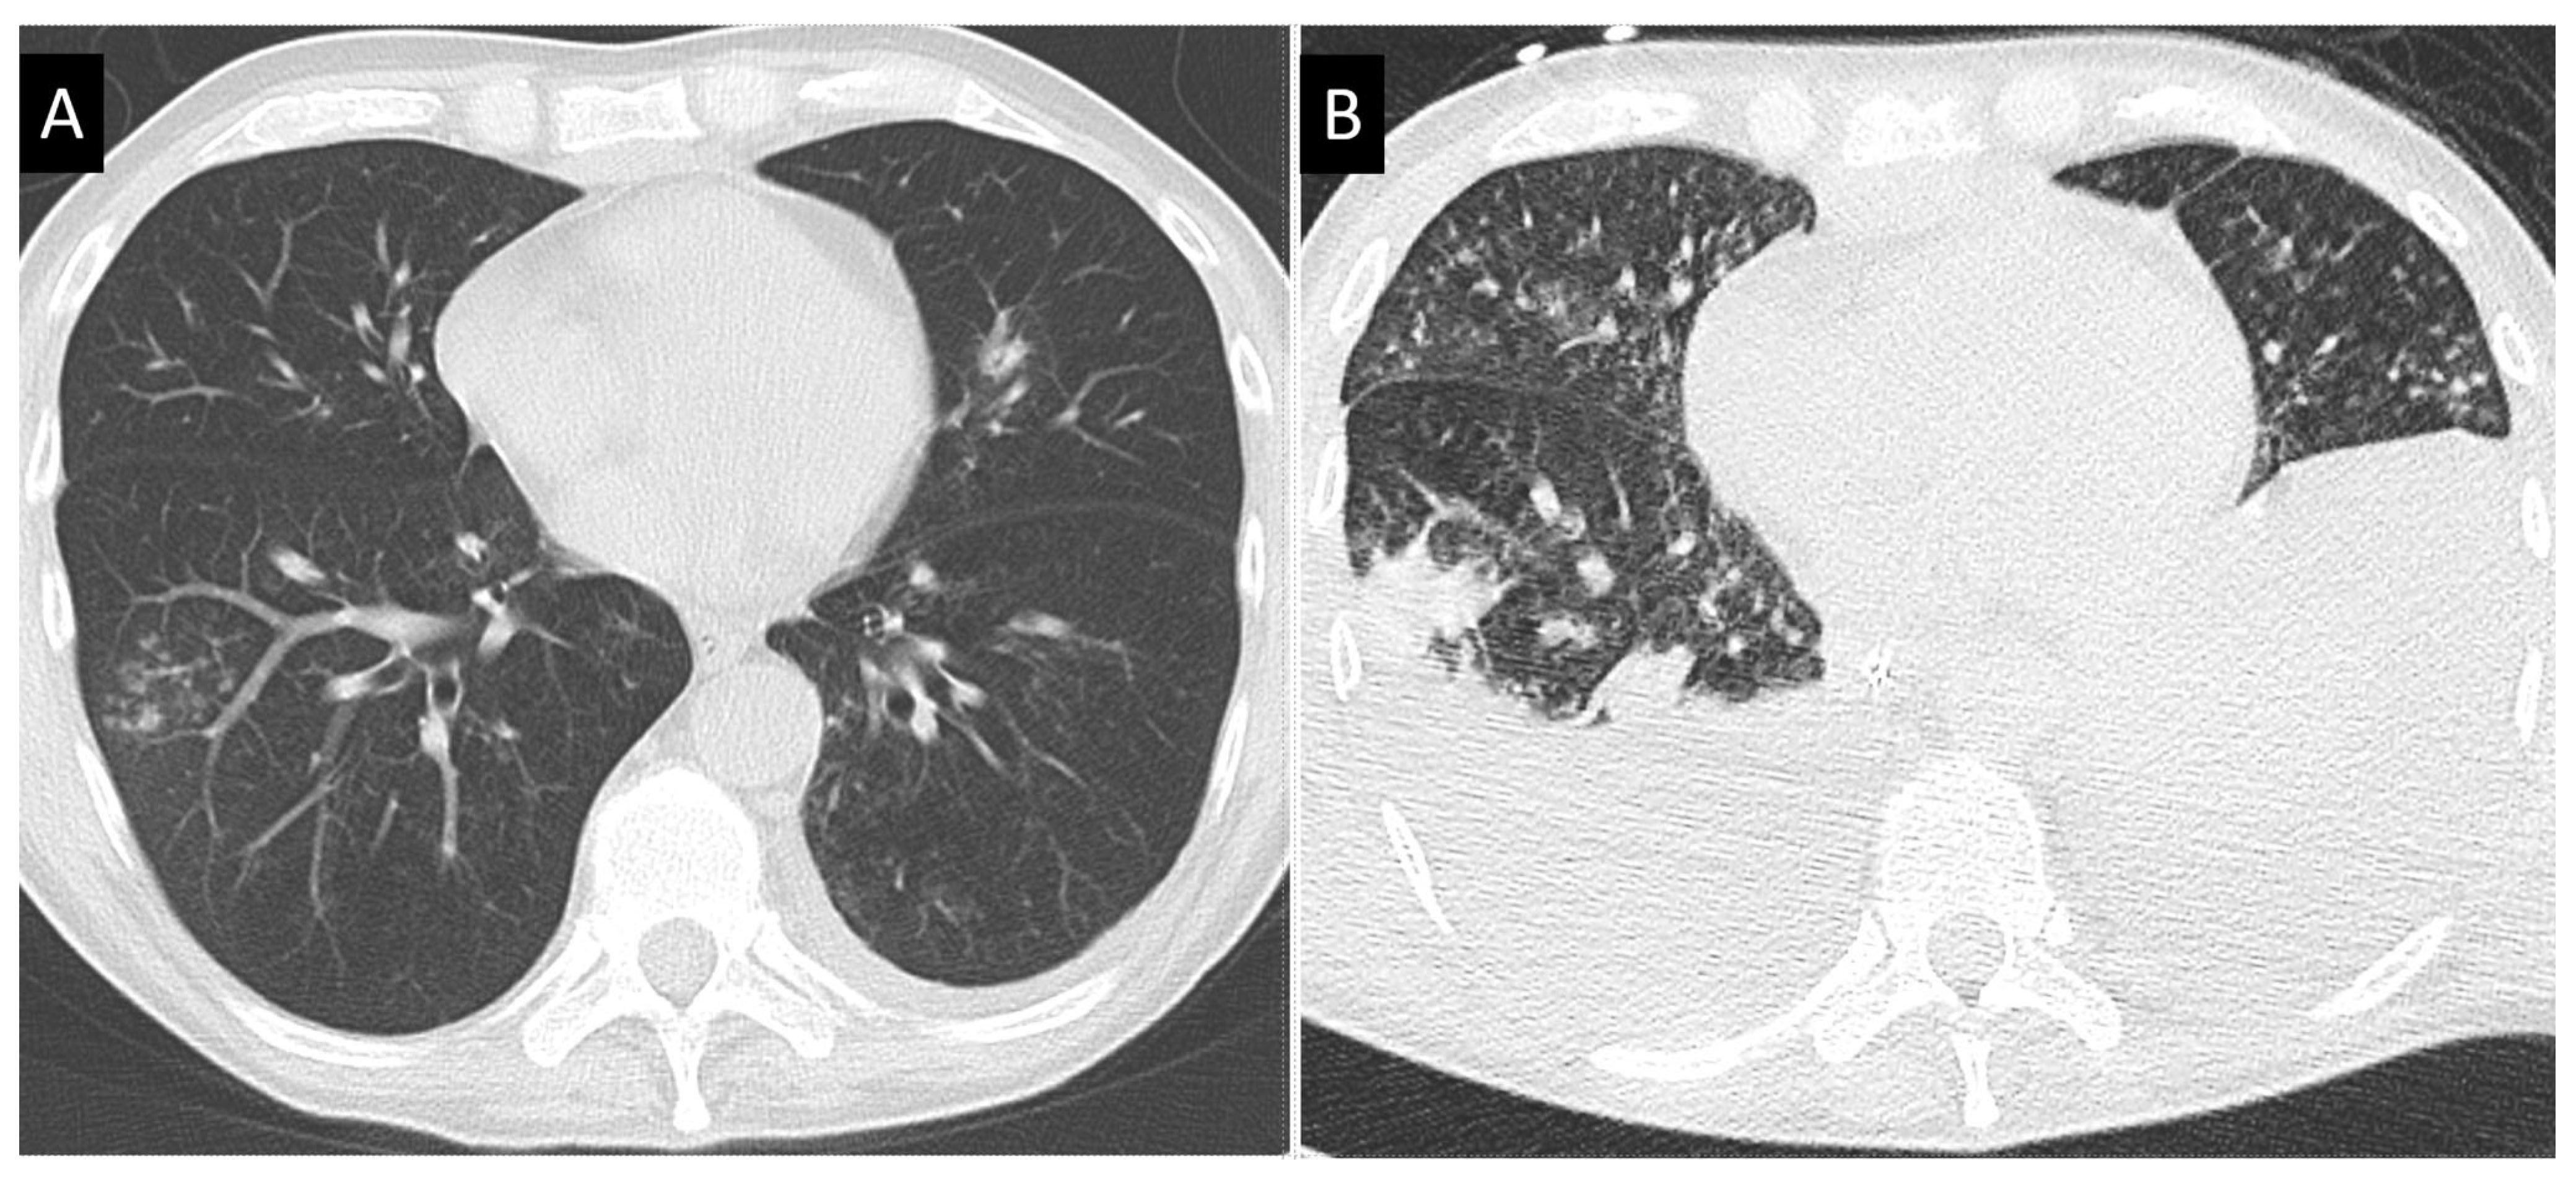

- Greene, R.E.; Schlamm, H.T.; Oestmann, J.-W.; Stark, P.; Durand, C.; Lortholary, O.; Wingard, J.R.; Herbrecht, R.; Ribaud, P.; Patterson, T.F.; et al. Imaging findings in acute invasive pulmonary aspergillosis: Clinical significance of the halo sign. Clin. Infect. Dis. 2007, 44, 373–379. [Google Scholar] [CrossRef]

- Prasad, A.; Agarwal, K.; Deepak, D.; Atwal, S.S. Pulmonary aspergillosis: What CT can offer before it is too late! J. Clin. Diagn. Res. 2016, 10, TE01–TE05. [Google Scholar] [CrossRef]

- Herbrecht, R.; Guffroy, B.; Danion, F.; Venkatasamy, A.; Simand, C.; LeDoux, M.-P. Validation by real-life data of the new radiological criteria of the revised and updated consensus definition for invasive fungal diseases. Clin. Infect. Dis. 2020, 71, 2773–2774. [Google Scholar] [CrossRef]